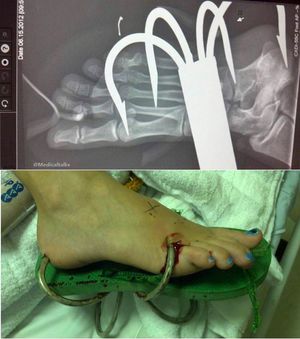

While most people are suffering from fishhook injuries, which are small and only penetrate superficially, this patient was unlucky to have this large shark hook deeply embedded in her foot! Although this hook can not be missed easily, identification of a other smaller fish hooks can be difficult, depending on the type and location of the wound and the timing and mechanism of injury. Soft tissue foreign bodies most commonly occur secondary to penetrating or abrasive trauma, and they can result in patient discomfort, deformity, delayed wound healing, localized and systemic infection, and further trauma during attempts at removal. Physical examination of the affected area should adequately assess for nerve, tendon, vessel, and joint involvement. Adequate local anesthesia and proper irrigation are important factors in controlling the pain and reducing the risk of would infection upon and after the removal of the foreign object. Large volumes of irrigant (sterile isotonic saline) at sufficient pressures is needed to reduce or eliminate particulate matter and foreign bodies, which, if left in the wound, can reduce the inoculum of bacteria required to cause infection. No single technique is best for the removal of foreign bodies. Each case is addressed independently based on the patient’s medical history and the clinical presentation of the wound.